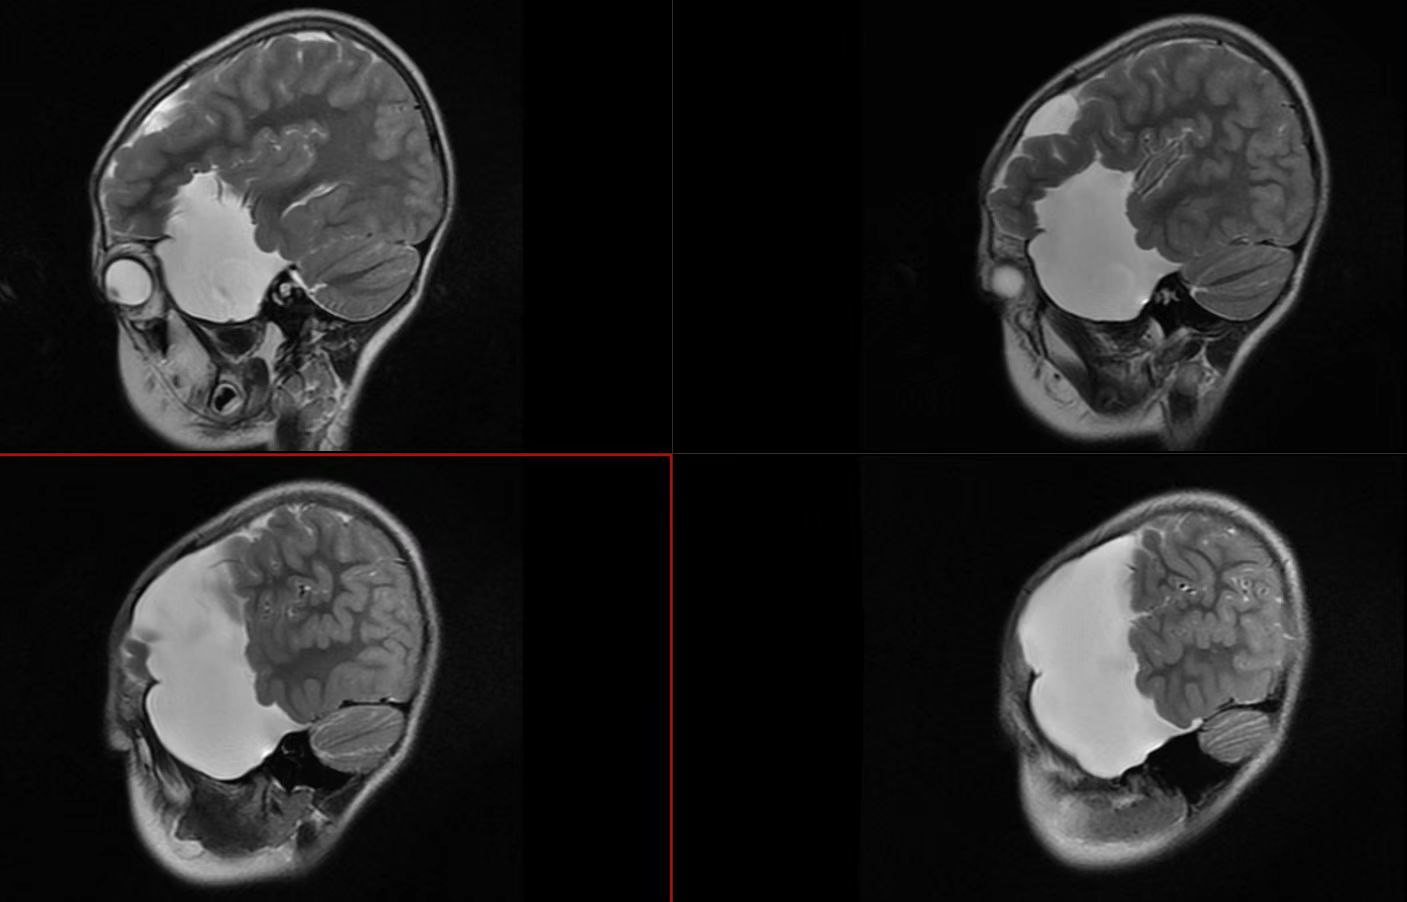

2019.8月颅脑核磁共振(脑内白色均匀信号为蛛网膜囊肿)